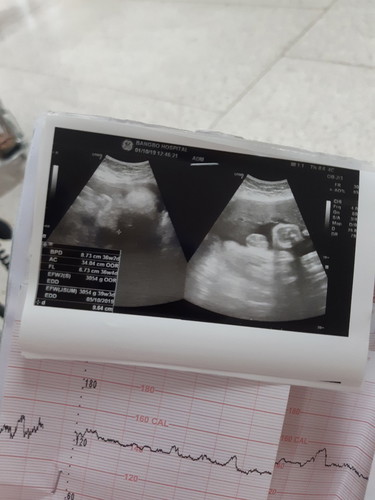

ใบซาวล่าสุด น้องน้ำหนักเท่าไหร่คะ แม่ลืมถามหมอ หมอก็รีบไปดูเคส รบกวนแม่ๆที่ทราบข้อมูลหน่อยค่ะ

3,054 กรัมคะ ดูตรง EFWคะ